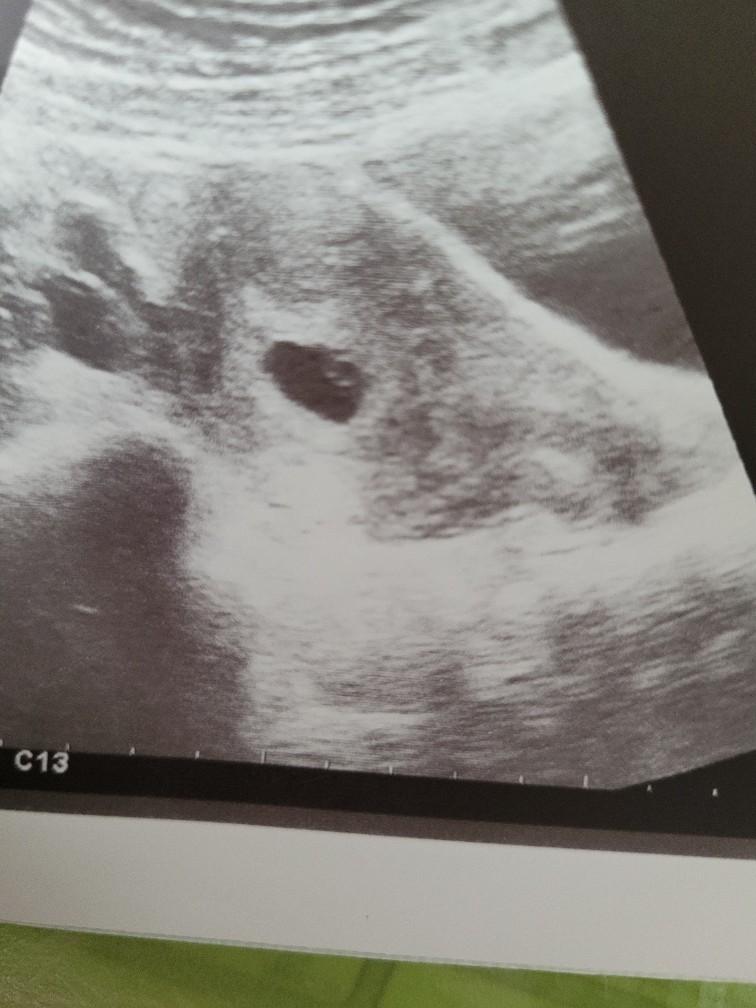

To zdjęcie wygląda jak głową sarny, a miejsce na pęcherzyk to okoTo jest moje usg w ciąży z pierwszym synem w 5 tc. Nawet nie opisali bo prawie nic nie widaćZobacz załącznik 1371193

Czyli na USG przynajmniej sam pęcherzyk powinien być widocznyHej dziewczyny. Zrobilam dzis powtórkę bety, jest przyrost i troszke mi ulżyło